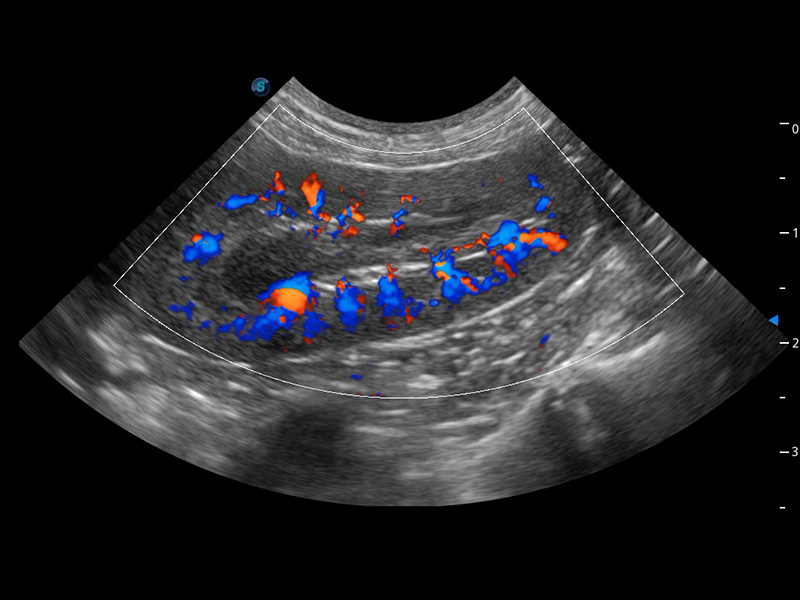

ProPet 60 作为一款高端台式动物超声设备,为动物医生的日常诊断提供了一系列贴合动物临床需求、解决临床实际问题的高级成像功能。凭借全系列高清探头,满足医生对腹部、心脏、生殖、浅表、肌骨等成像的所有需求,切实帮助您提升检查效率,提高诊断信心。

兽用彩色多普勒超声诊断系统

动物是人类最亲密的朋友和最值得信赖的伙伴。玖鼎集团也一直致力于探索动物专用的超声影像解决方案。 全新推出的ProPet系列,是玖鼎集团在动物超声影像智能化、专业化、精准化的一次跨越式革新。动物不能用言语来表述自己的不适,通过超声影像,ProPet系列搭建了动物医生与不同物种沟通的“桥梁”,为动物医生注入了“治愈之力”。